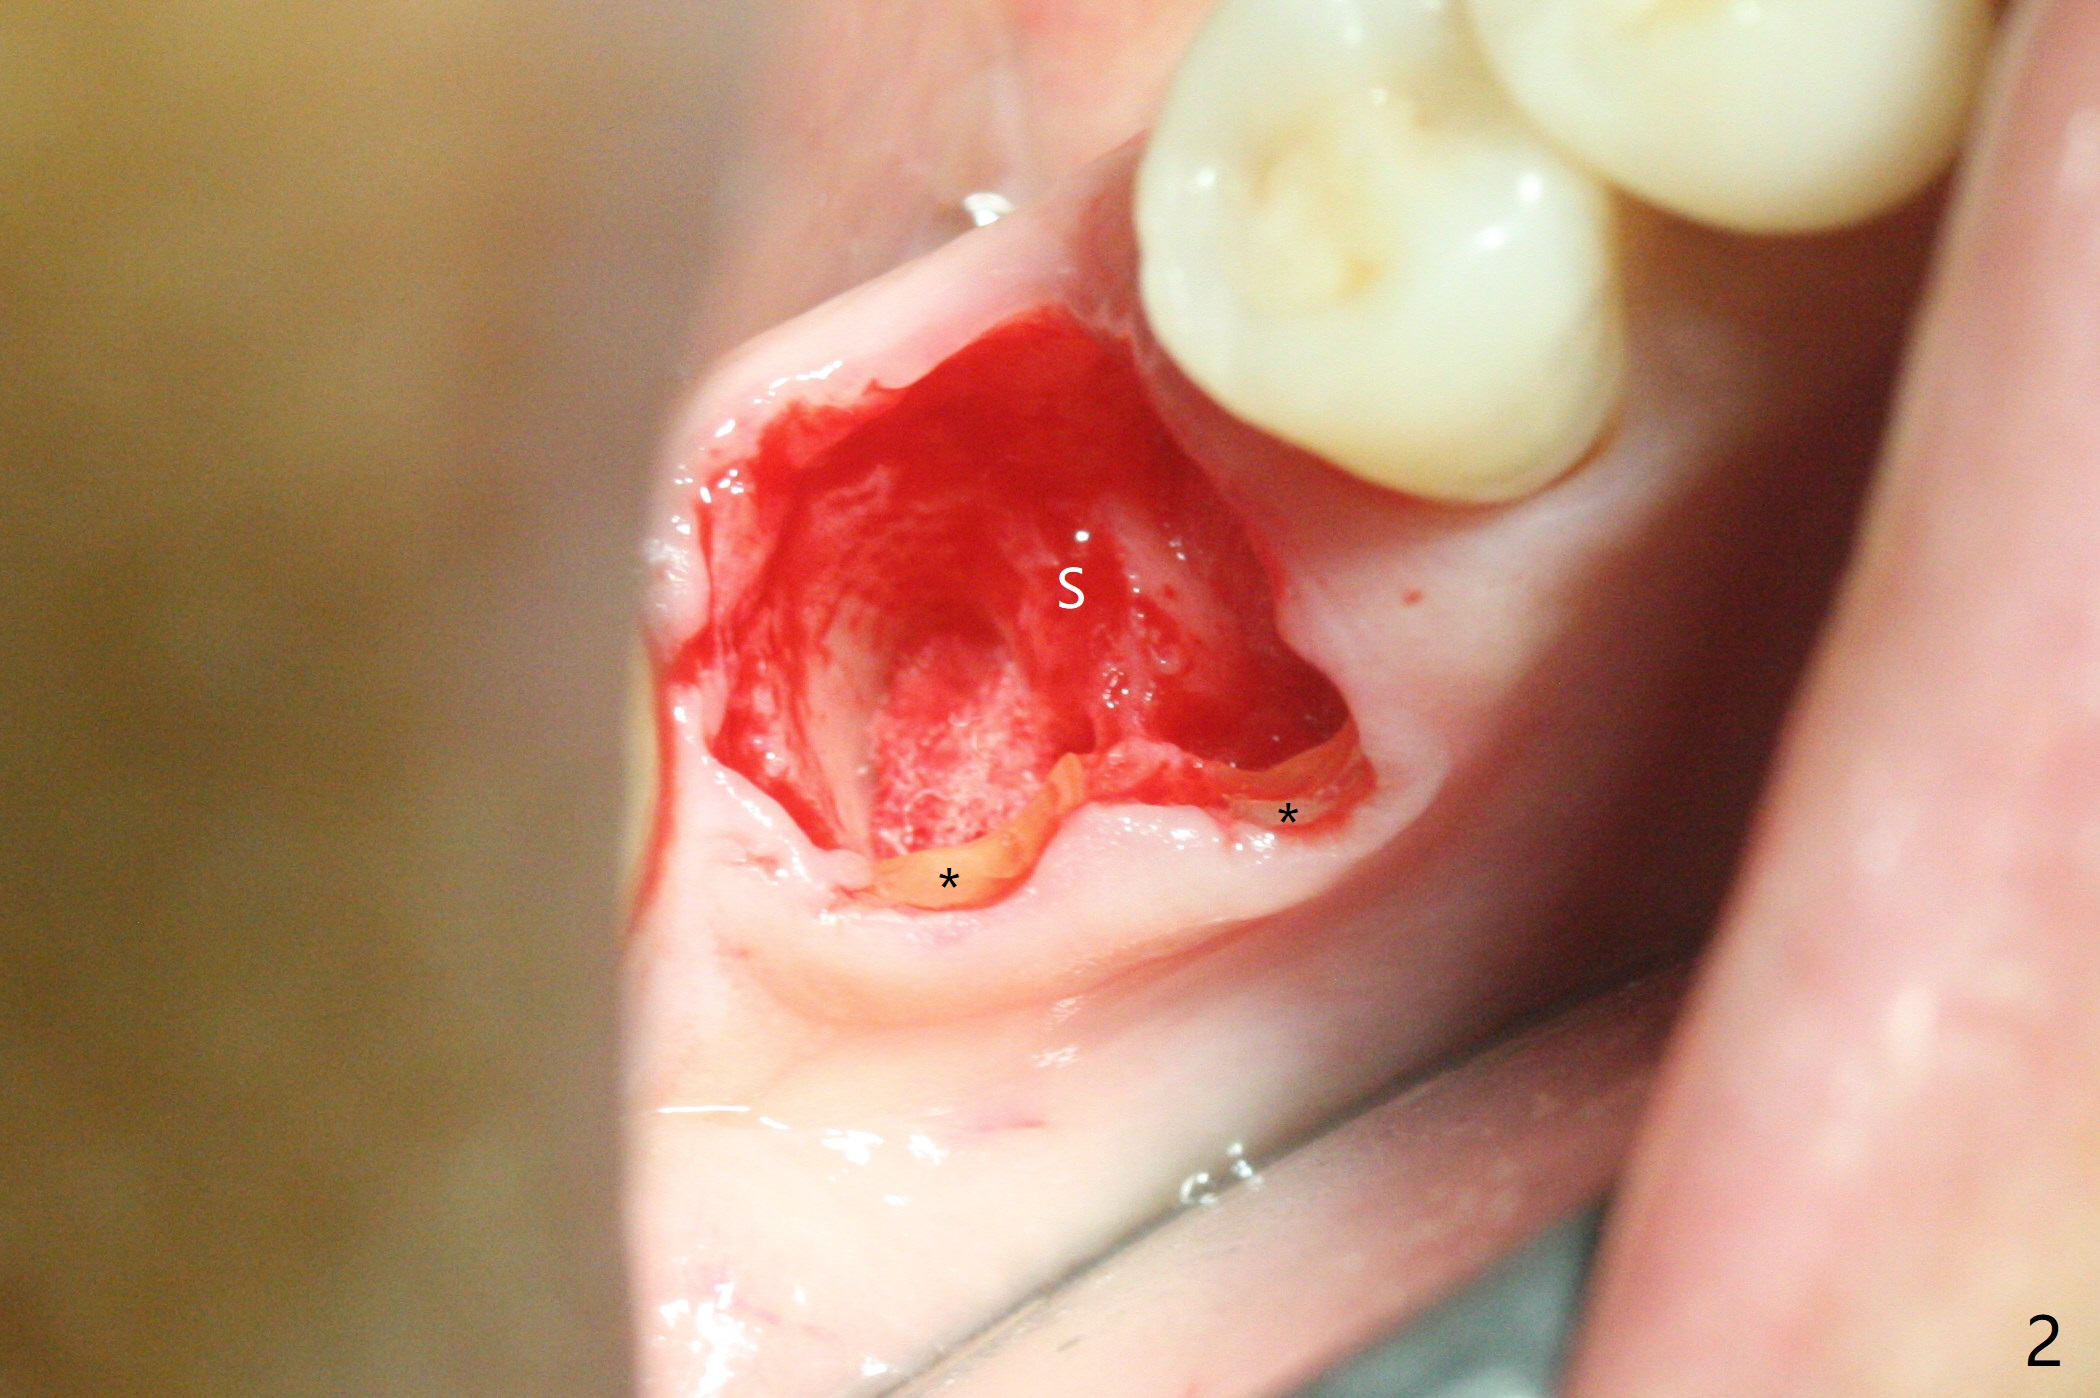

To prevent further postop buccal gingival recession at #30, socket shield is formed with removal of the residual roots (Fig.1,2 *). Osteotomy is initiated in the septum (Fig.2 S, to be flattened with bone trimmer and surgical round bur) and gradually slides slightly into the mesial socket in spite of using surgical guide (Fig.3 *: sleeve). Following 4.5x11.5 mm drill, a 4.5x8 mm Bicon implant is pressed fit; its stability is lightly enhanced with placement of sticky bone in the remaining sockets (Fig.4 *) and around the black plug (Fig.5 P). After removing the coronal portion of the plug to reduce occlusal interference, two pieces of PRF are wrapped around the remaining plug (Fig.6). The main stability of the implant is obtained when setting acrylic (A in Fig.7) is applied into the edentulous space (undercut). After acrylic setting, flowable composite (*) is added distal for further retention. One month postop, the flowable composite is detached. The provisional is sectioned; the black plug is cut. The socket heals with exposure of the mesial socket shield (Fig.8 >). The black healing plug and the mesial socket shield remains exposed 3 months postop (Fig.9). When a 4.5x6.5 mm temporary abutment is placed, the buccal gingiva is blanched and the mesial socket shield is pushed buccal (Fig.10). The implant appears to remain covered by the bone 3 months postop (Fig.11). Cortical bone starts to form crestal 7 months postop (Fig.12 arrowheads, coronavirus). The cortex seems to thicken 8 months postop (Fig.13 *).